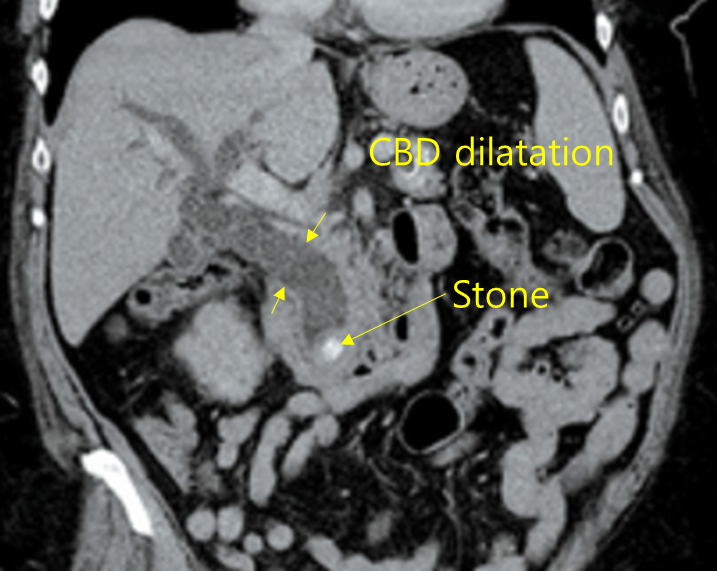

Img | CT: 담관 확장, 담관내 결석 |

RUQ pain과 발열을 주소로 내원한 환자로, 공막 황달이 확인되므로 Charcot’s triad를 만족하고, 급성 담관염을 의심할 수 있다. 혈액검사에서도 담즙정체를 시사하는 총빌리루빈과 ALP의 상승이 확인되고, 결정적으로 복부 CT에서 담관내 담석 및 이에 의한 담관 확장을 관찰할 수 있다. 담석에 의한 급성 담관염은 ERCP를 통한 내시경온쓸개관돌제거술로 치료하여야 한다.

진단 | • US/CT: Bile duct dilatation, stone이 보일 수도 있음 • MRCP/ERCP: Proximal bile duct dilatation, filling defect 등 |